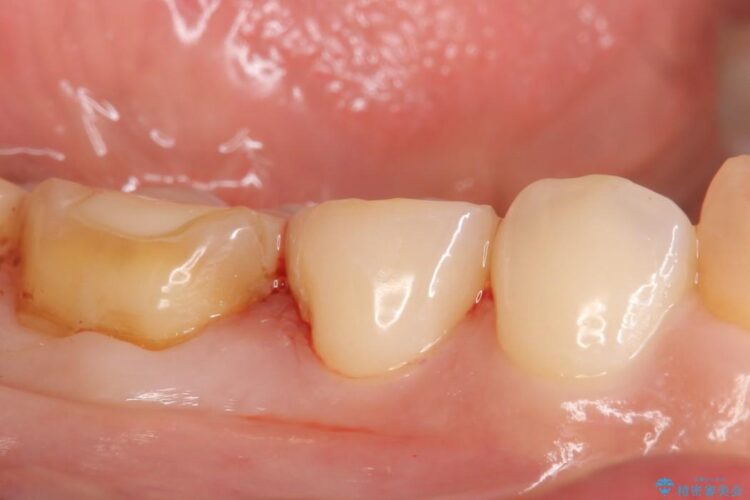

治療後について

詰め物の下に隙間がある場合、隙間に細菌が侵入し虫歯が再発してしまう可能性があります。また、詰め物が割れたり外れたりしてしまう危険性もあります。

ですのでもし隙間が見つかった場合には再度治療をすることをお勧めいたします。

治療完了した歯でも、時間の経過や力的作用によってセメントが変性したり、隙間が空くことによって詰め物の下に虫歯が発生したりすることがあります。

そうならないためにも適合の良い剛性にも優れた素材を用いた治療を求められます。特にセラミックが使用されたインレーは見た目が自然なだけでなく適合性、剛性共に高い水準を持つためリスクを減らすことができます。